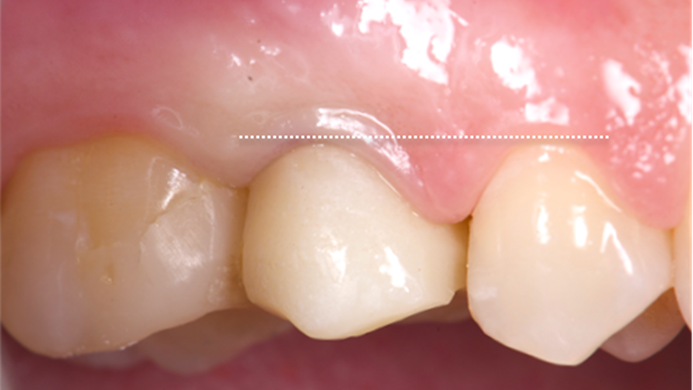

Clinical case: Digital Data Save concept in upper jaw premolar area

- Courtesy of Dr. Lysov Alexander Dmitrievich & Dr. Sofronov Matvey Vitalievich, Russia -

AnyRidge, R2GATE, R2GATE guide, ISQ value, initial stability, immediate loading, KnifeThread, maxillary posterior, #14, Digital, Dr. Lysov Alexander Dmitrievich, Dr. Sofronov Matvey Vitalievich, zirconia abutment, CAD/CAM crown

Products used

AnyRidge implant system, R2GATE, Digital prosthesis

“AnyRidge & R2GATE show stable results

after immediate extraction, immediate implant placement, & immediate loading,

even with low bone density.”